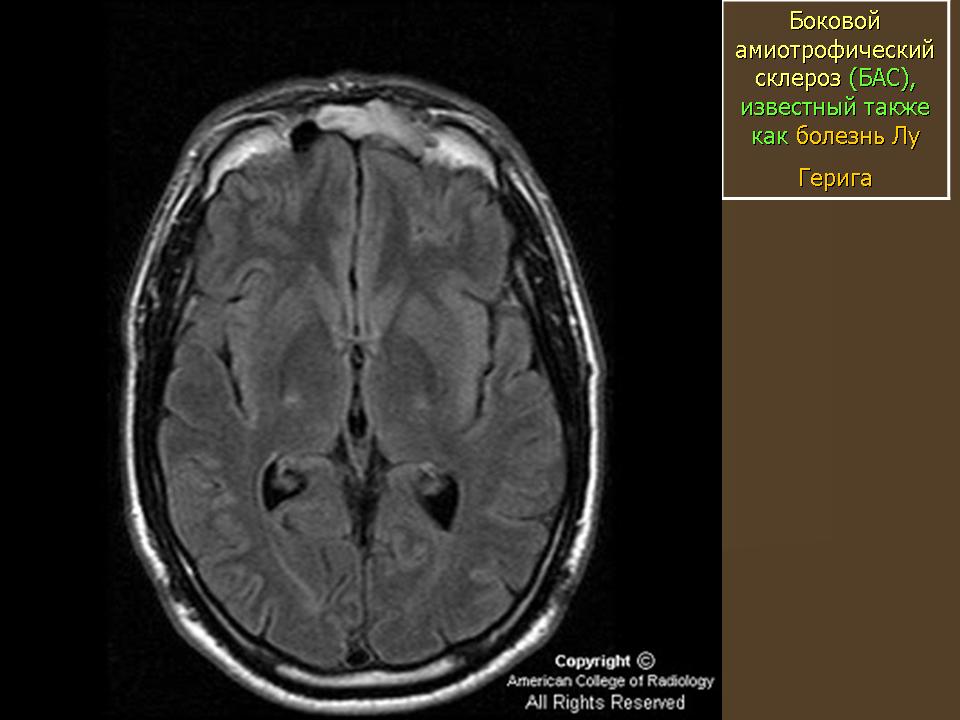

Официальное название заболевания - боковой ами-отрофический склероз (БАС), однако в США оно больше известно под названием «болезнь Лу Герига». Это прогрессирующее нейродегенеративное расстройство было диагностировано в 1939 г. у легендарного американского бейсболиста с таким именем, полевого игрока команды «Нью-Йорк Ян-киз», прожившего после появления первых симптомов всего два года. БАС начинается с повреждения нервных клеток, идущих от головного и спинного мозга к мышцам всех органов и тканей. Когда так называемые двигательные нейроны погибают, головной мозг оказывается не в состоянии управлять работой мышц, и наступает полный паралич.

Представление о том, что такое боковой амиотрофический склероз, дает само название болезни. «Амиотрофический» состоит из трех греческих слов. «А» - отрицание, «мио» - относящийся к мышцам, «трофика» - питание. Таким образом, мышцы у больных БАС испытывают дефицит питательных веществ, а потому атрофируются. Слово «боковой» указывает на область спинного мозга, в которой располагаются погибшие участки нервных клеток. С дегенерацией данной области происходит ее уплотнение («склероз» как раз и означает «затвердевание»). Возможно, самой ужасной особенностью заболевания является то, что больной не утрачивает умственны-ех способностей и осознает все, что с ним происходит.

Наиболее распространена спорадическая форма БАС. Кажется, что болезнь может настичь кого угодно и в любое время. Наследственная форма встречается лишь у 5-10% больных. Ранние проявления заболевания у разных пациентов могут быть неодинаковы, но обычно все начинается со слабости в руках и ногах, речевых расстройств, мышечных судорог, ограниченности движений. Как только затрагиваются дыхательные мышцы, больного помещают в стационар и переводят на искусственную вентиляцию легких.

При БАС поражаются только двигательные нейроны, а чувствительность, слух, вкусовые ощущения и обоняние сохраняются. Однако мотонейроны, ответственные за произвольные движения глаз и мочеиспускание, по неизвестным причинам долгое время остаются ин-тактными. Хокинг, например, до сих пор контролирует сокращение глазных мышц; одно время он использовал для коммуникации брови, поднимая или опуская их в определенных ситуациях. Он может также шевелить двумя пальцами правой руки и использует их для управления синтезатором речи. Администрация по контролю над пищевыми продуктами и лекарственными средствами США (РАО) одобрила применение лишь одного препарата для лечения БАС. Это рилузол, вещество, продлевающее жизнь на несколько месяцев; скорее всего его действие состоит в подавлении образования вредных химических соединений, повреждающих двигательные нейроны.